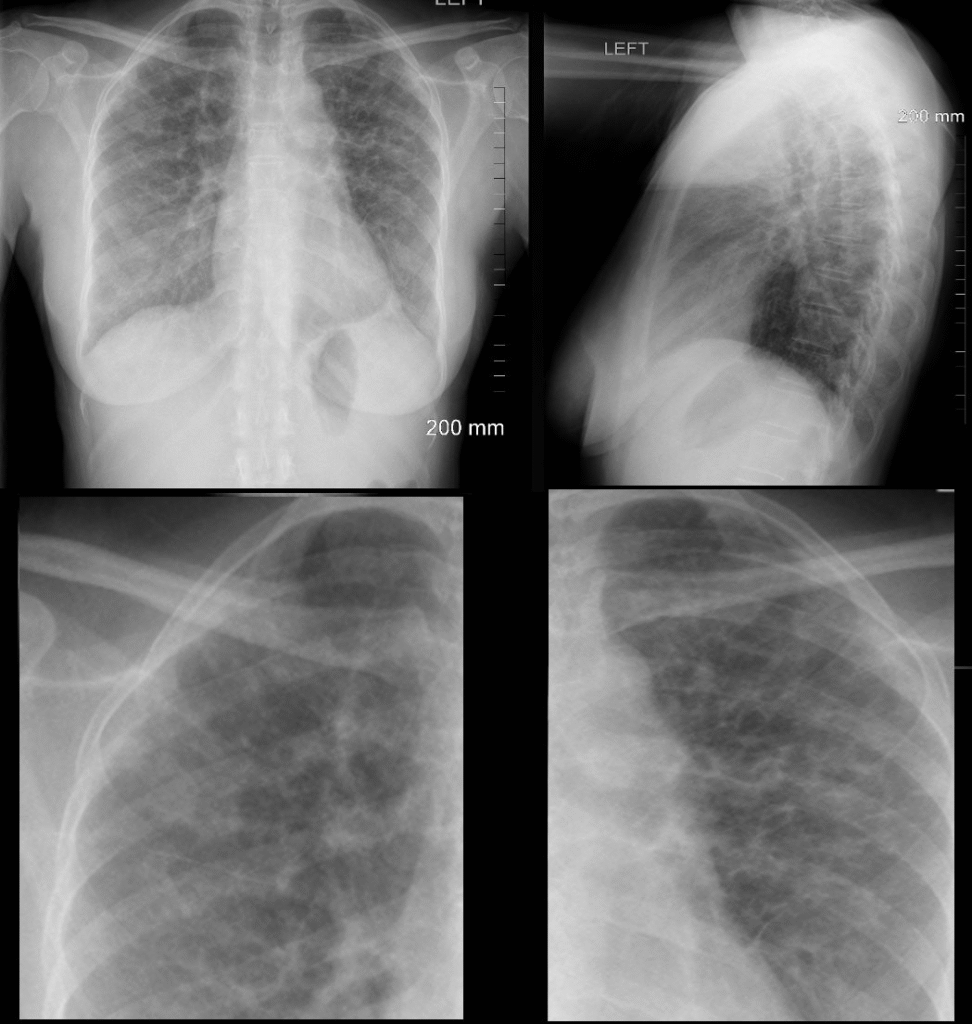

- Rö-Thorax: retikuläre Zeichnungsvermehrung

- HRCT (Goldstandard): „honigwabenartige“ Veränderungen (v. a. bei IPF)